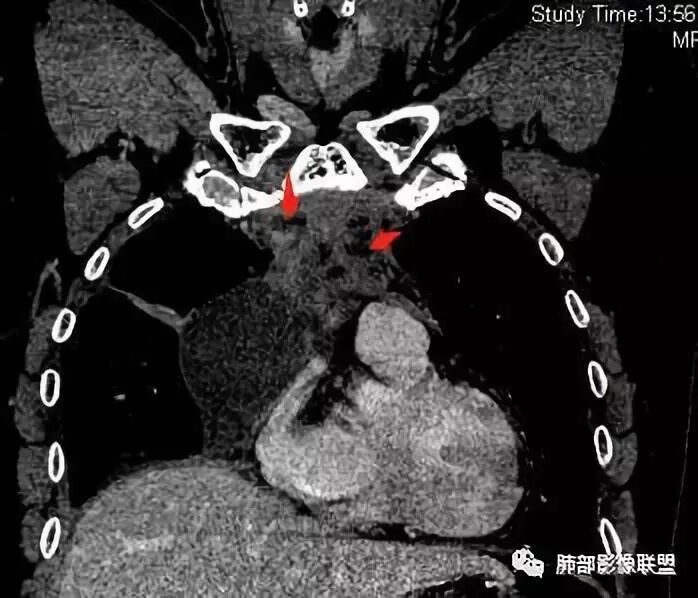

南边:大家看看前纵隔的病灶,符合肿瘤吗脂肪,周围密度增高

三个石头:比较散;像炎症的蔓延生长南边:是,这些看着心里不踏实觉得把这个纳入肿瘤去考虑是否合适总觉得边缘收缩的、散在的朝周围蔓延;中央还跨过脂肪,朝对侧胸膜蔓延把这个与囊性病变连到一起去考虑是否还需要斟酌一下因为这个就方向差异大了南边:连在一起,囊实性,边界不清,自然考虑恶性:如果独立,囊张力高、边界清楚,间隔,自然朝良性考虑:

Coke with ice:囊性部分考虑包裹性积液?南边:不是积液;有间隔;张力高;而且位置有些特殊

大家仔细看看积液中的游离气体;

不是支气管,是积气;是穿刺进去的;

囊内密度不一致

我认为囊张力高,积液中的气体均在周围,外侧、下方,囊内有间隔:各腔密度不一致;提示:囊腔属于前纵隔,不是包裹性积液;现在的问题:囊腔与内侧的病灶是否是一体的

南边:我总觉得这个纵隔内不像是一个肿块的改变,扁平,周围蔓延:有符合炎性的的特点,或者肿瘤的侵犯;但是肿瘤的侵犯,不大符合,实性部位的边缘过于柔和,没有毛糙的侵犯边缘。

2、前纵隔内病灶囊实性混杂密度病灶,囊性病灶主要位于右侧,张力较高,有分隔影,囊壁右侧缘光整,病灶左侧实性部分边界不清明显强化,病灶肺瘤交界面大部分边界清楚,部分模糊。

纵隔内病灶不符合肺癌转移途径,且纵隔内单发的囊实性转移罕见。淋巴瘤无论是分布、形态、密度、还是强化方式度不符合。

患者缺乏纵隔炎的临床表现,囊性病损更难以解释。

胸腺瘤/胸腺癌:病灶内那么大的囊,常规考虑B型以上胸腺瘤,囊内有分隔影,病灶周围脂肪间隙模糊,常规考虑侵袭性胸腺瘤或胸腺癌,若侵袭性胸腺瘤,常侵犯胸膜、心包,很少累及肺。胸腺癌易侵犯胸膜、肺并纵隔淋巴结及远处转移。但肺内腺癌形态更符合原发灶。胸膜及叶间裂转移则即可来自肺,也可来自胸腺癌。